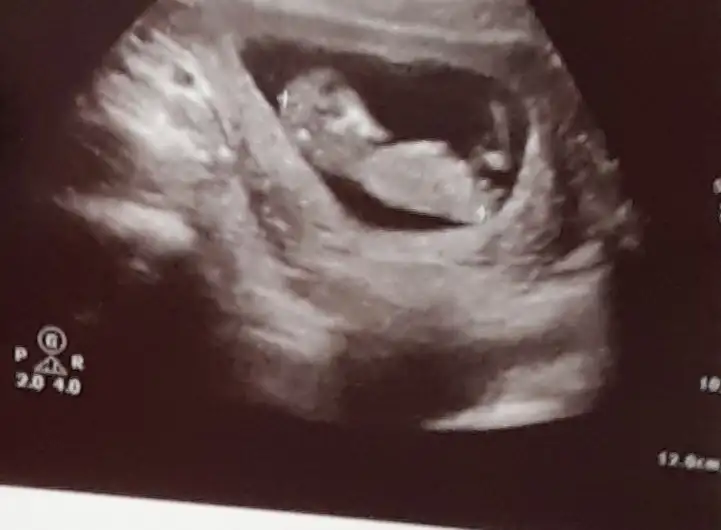

Eklentiler

• 20201023_150518.webp

20201023_150518.webp

34,4 KB · Görüntüleme: 80

• 20201023_150459.webp

20201023_150459.webp

40,8 KB · Görüntüleme: 79

Doktor erkek dedi ama 12.hafta olunca ben emin olamadım. Pipi fotosu da vermiş, ona da bakınca çok emin olamıyorum. Belli bir aya dek benzer gittiği için genital organlar, belki yanılmıştır diyorum..kız istediğim için..umarım bir ay sonra, yanılmışım, kızmış der doktor..